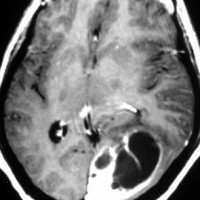

40代女性の後頭部傍矢状洞部の硬膜に発生したグレード3です。腫瘍周囲の強い浮腫のために,頭頂葉のゲルストマン症候で発症しました。術前診断は髄膜腫でしたが,腫瘍内部にのう胞(液体が溜まっている)があり,髄膜腫としては典型的な画像ではありません。右側の血管撮影にみられるように,上矢状洞が一部狭窄して腫瘍が浸潤している所見があり,腫瘍が濃染します。腫瘍の周囲の脳には出血がありました。大脳鎌と上矢状洞の壁を含めて全摘出しました。